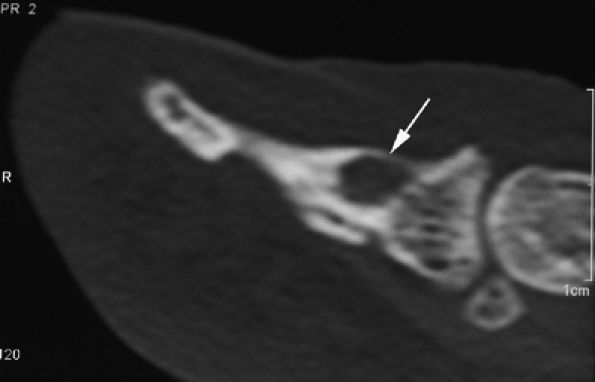

|

FIGURE 11.98 ● Osteoid osteoma of the distal phalanx. CT scans showing the osteolytic noncalcified nidus (arrow).

soft tissues, the nidus may be difficult to highlight with MR imaging (Fig. 11.99). Percutaneous radiofrequency ablation may be performed in the tubular bones of the hand.250